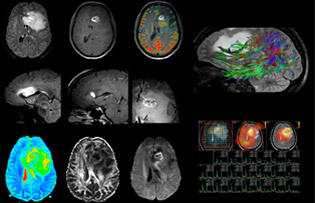

Comprehensive exam answers complex brain tumor questions

Dr. Savatovsky uses five or six different ExamCards for imaging a mass or a known tumor in the brain. “If there is a mass in the brain we try to characterize it to inform the neurologist for determining next steps or to help neurosurgeon prepare for a surgery or biopsy. For follow-up after treatment we have different protocols for different treatments and we adapt for intra- or extra-axial tumors.”

“The biggest challenges are properly characterizing the lesion and giving the surgeon all the information needed, such as the location of vessels and functional areas. Sometimes a very comprehensive exam is necessary, such as when a mass has been discovered at another hospital after which the patient is referred to us. We then do both lesion characterization and preoperative imaging in one exam, so both morphologic and functional assessment. For morphologic assessment we will use pre- and post-contrast T1-weighted imaging, FLAIR to assess infiltration, and diffusion. For functional characterization we will perform perfusion, spectroscopy, and susceptibility weighted imaging to look for micro vessels or micro hemorrhage inside the lesion[4]. For preoperative imaging we perform specific morphologic imaging that is compatible with the navigation system; depending on the location of the tumor, we would do fMRI or DTI.”

“That is the most comprehensive exam we would do. Ingenia has the good spatial resolution and high SNR to provide all this information, and the flexibility to use shorter sequences, so we can do a very comprehensive examination in a limited time.”